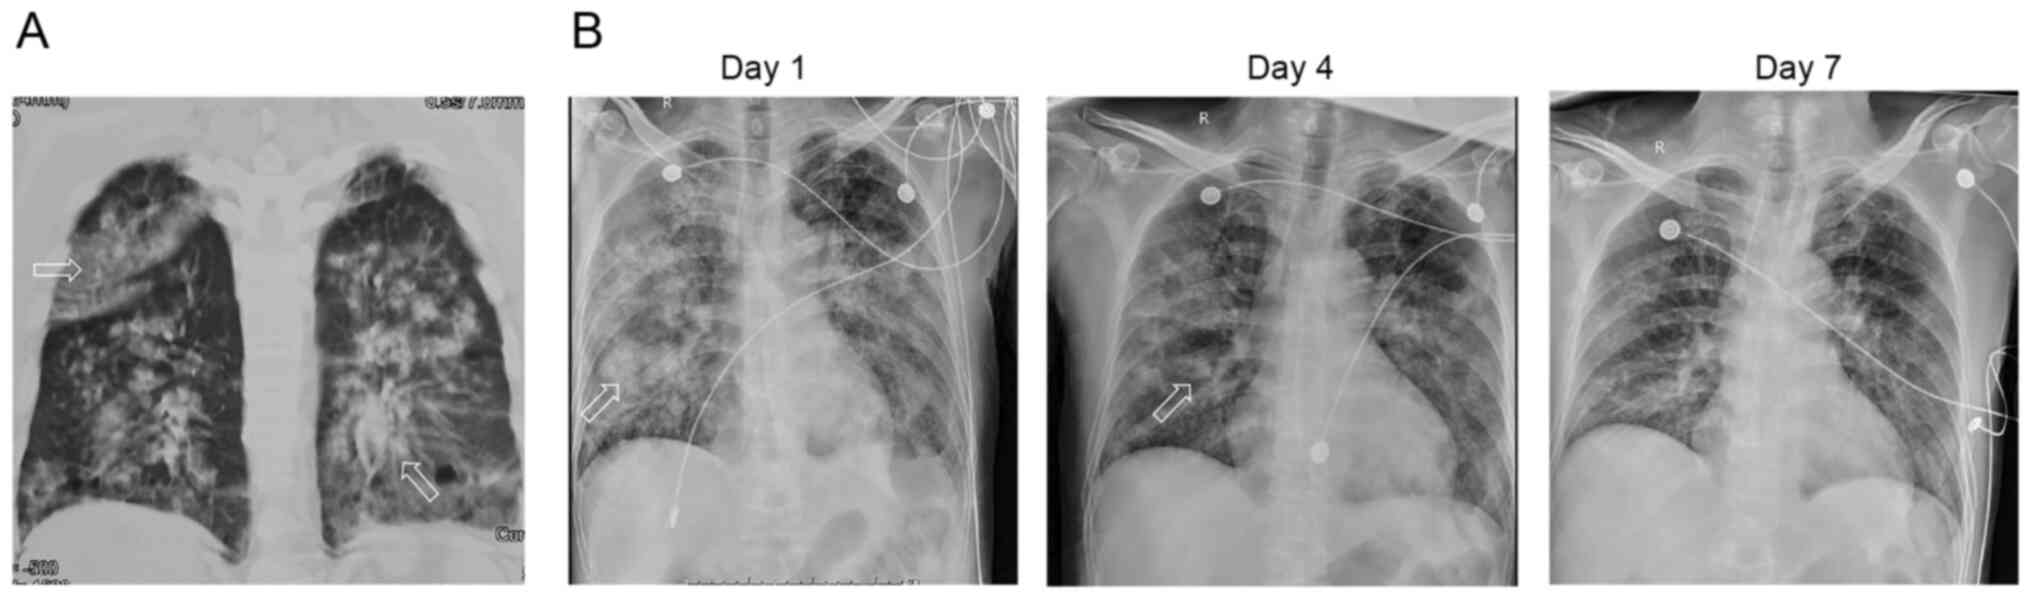

Figure 2

Chest CT of Case 2. (A) CT scan performed on arrival to the Emergency Department ~3 h after drowning, revealing both lung interstitial opacities with air trapping. (B) CT scan performed on the seventh day after treatment showed a few fibers cable shadows and pulmonary nodules. The arrows represent exudative changes in the lungs.

A 60-year-old woman was brought to the emergency department of Tongji Hospital (Wuhan, China) in January 2022 after nearly drowning in a pool. Witnesses reported that she had been underwater for ~10 min. After vomiting a lot of sewage, the patient gradually recovered and developed dyspnea and limb weakness over the next 3 h. Upon arrival at the emergency department, the patient presented SpO2, 88%; P/F, 100; BP, 130/80 mmHg; pulse 98/min; and RR, 26 breaths/min, without fever or rales. Chest CT revealed bilateral alveolar opacity (Fig. 2A).

Based on the successful treatment protocol presented in case 1, the patient was prescribed for 7 days: 40 mg/day methylprednisolone; 0.1 g sivelestat sodium three times a day using an intravenous pump under mild ARDS diagnosis (nasal high-flow oxygen, P/F284) performed within 24 h, according to the aforementioned drug indications, with 0.3 g biapenem every 8 h and 0.6 g levofloxacin. The patient did not have underlying COPD or other diseases, and high-flow oxygen was solely used as a means of respiratory support, providing no therapeutic role. Following 7 days of treatment, the patient showed significant clinical and radiological improvement, including ABG test results as pH, 7.422; PaO2, 92 mmHg; PaCO2, 44.8 mmHg; SaO2, 97%; and P/F, 284. Laboratory examination showed: WBC count, 11.71x109/l; and PCT, 0.22 ng/ml. A chest CT showed the resolution of most of the interstitial opacities (Fig. 2B). Microbiological analysis of the sputum and serum showed negative results. The nasal high-flow oxygen was discontinued and the patient was discharged after 3 days.